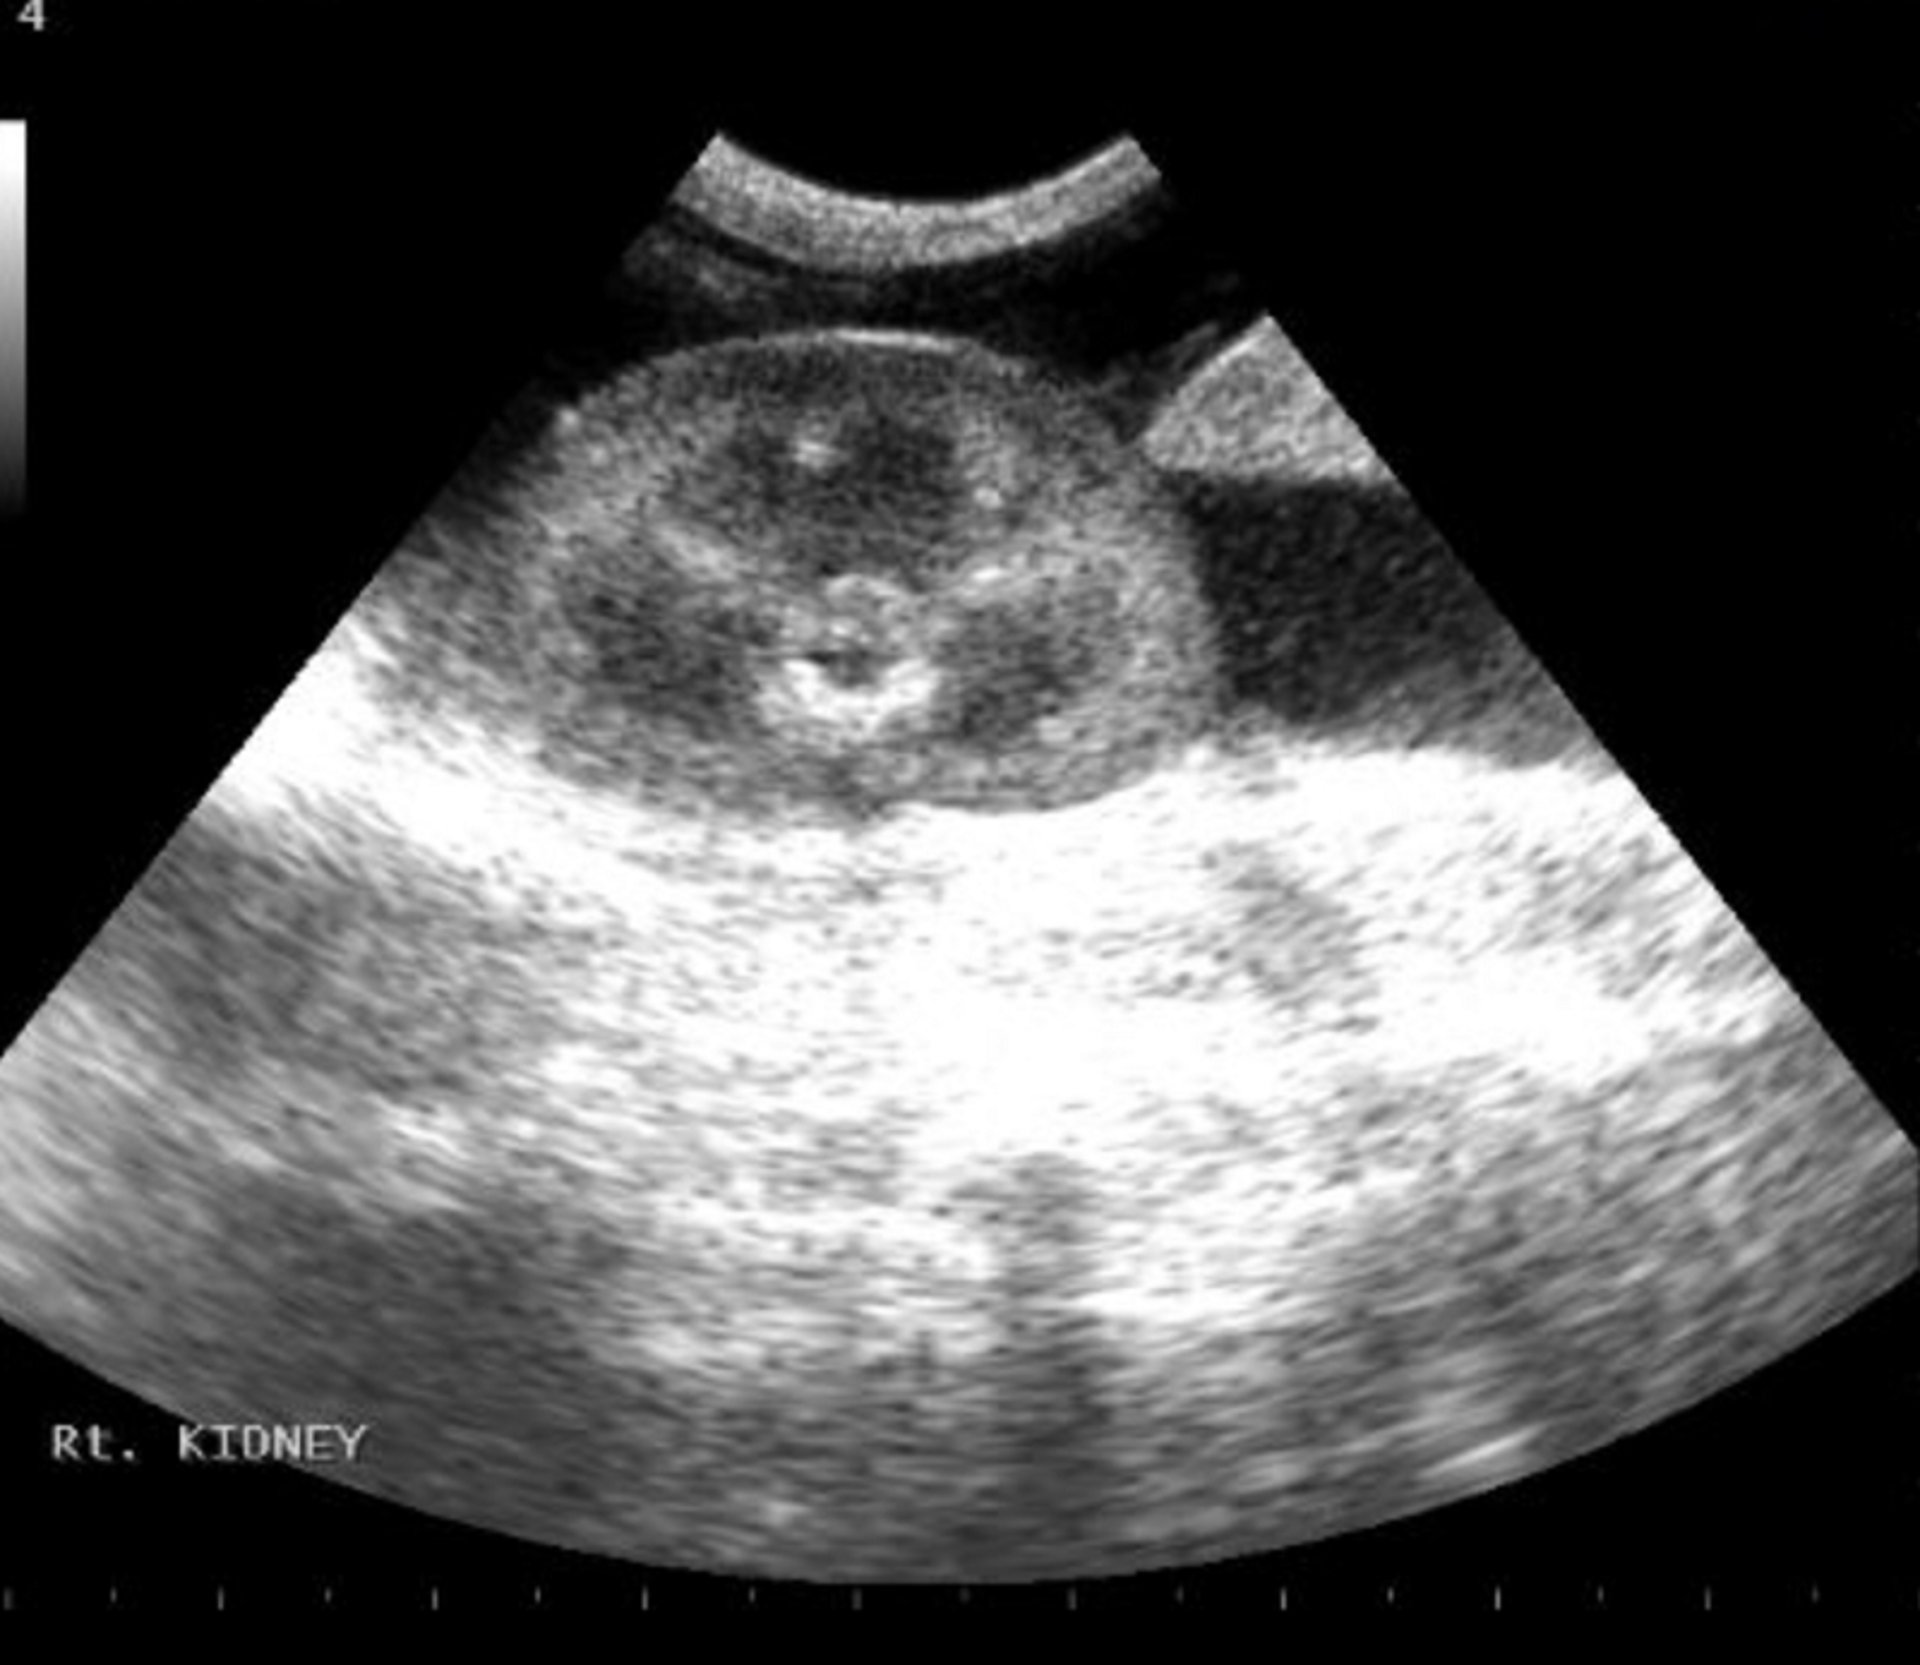

Imagen de una ecografía abdominal en el punto de atención que muestra una acumulación de líquido (negro/anecoico) alrededor del riñón derecho.

Cortesía del Dr. Andrew Linklater.